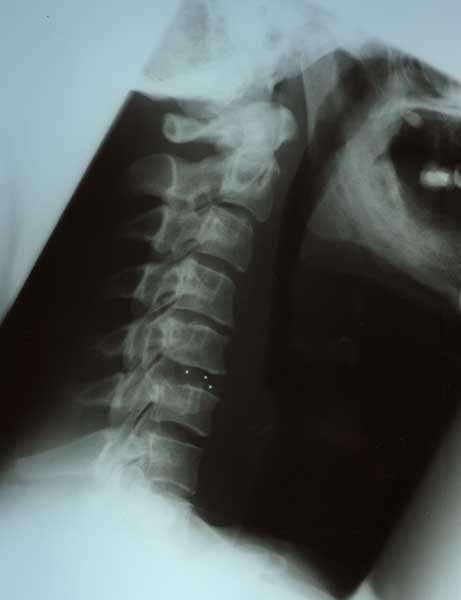

Bandscheibenvorfall HWS

Für Bandscheibenvorfälle im Halswirbelsäulenbereich gilt ähnliches wie im Lumbalbereich. Auch hier kann es durch die zunehmende Degeneration vor allem der unteren Halsbandscheiben zu einer Bandscheibenvorwölbung mit Kompression von empfindlichen Nervenstrukturen mit daraus folgenden Schmerzen im Nacken und Arm kommen. Auch hier kommt es durch geeignete konservative Therapiemaßnahmen in vielen Fällen innerhalb von 6 bis 8 Wochen zu einer deutlichen Besserung der geklagten Beschwerden. Falls eine Besserung nicht eintritt oder neurologische Defizite auftreten, ist nach Durchführung der erforderlichen Diagnostik (normale Röntgenaufnahme, Computertomographie oder Kernspintomographie) eine Operation anzuraten.

Die Entfernung des Bandscheibenvorfalls wird mikrochirurgisch unter Verwendung des Operationsmikroskopes und von Mikroinstrumenten durchgeführt.

Die Bandscheibe wird durch ein Titan - Implantat ersetzt.Diese Implantate führen zu einem Zusammenwachsen der angrenzenden Wirbelkörper ohne das dadurch die Beweglichkeit der gesamten Wirbelsäule spürbar beeinträchtigt wird.